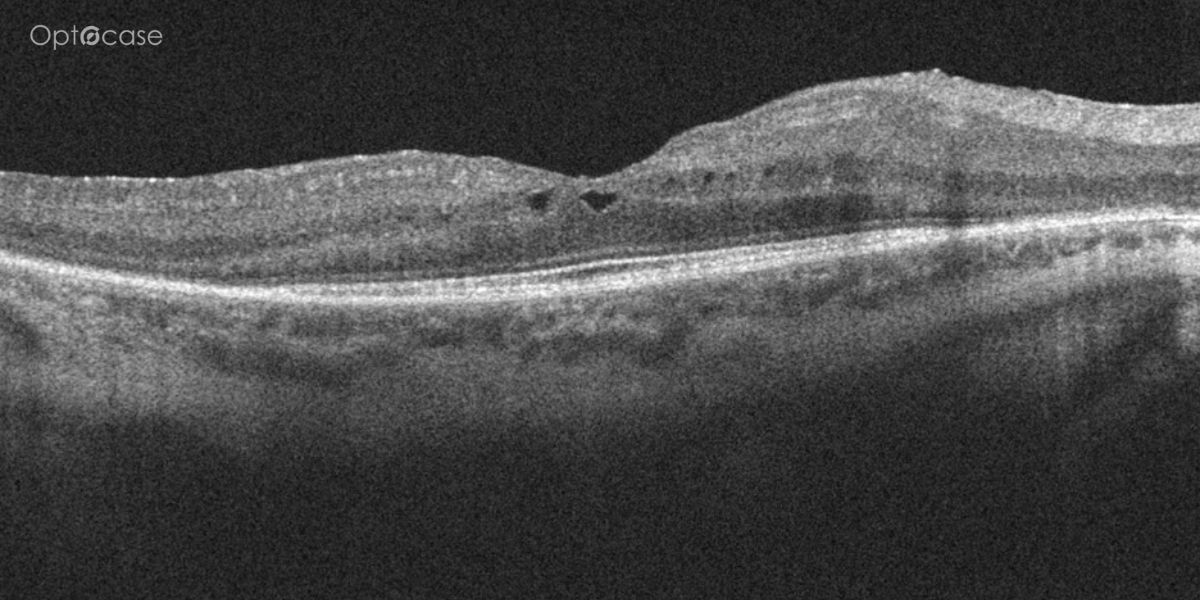

Here there is loss of the regular macular depression. There is a bright line present on the surface of the retina. In addition, there is separation of the retinal layers in the inner retina.

The patient was diagnosed with a schisis secondary to an epiretinal membrane. This complication is seen in over 50% of ERMs (video).

In any patient with intraretinal fluid consider the possibility of an epiretinal membrane causing a schisis.